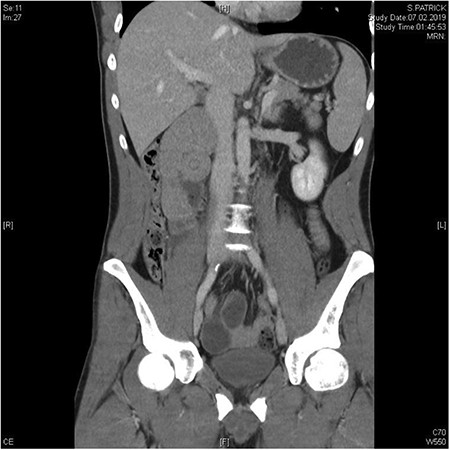

A 37-year-old patient presented with acute abdominal pain which was colicky in nature and accompanied by nausea and repeated vomiting. Physical examination showed tenderness in the right lower abdomen and guarding in all four quadrants. There was no history of previous abdominal surgery. A computed tomography (CT) scan revealed the mechanical obstruction of the small bowel and the suspicion of a pre-existing paraduodenal hernia in the right upper abdomen (Figs 1 and 2). Fortunately, the patient’s condition improved significantly following the administration of analgesia, and the initial conservative treatment was continued. An X-ray with oral contrast agent enhanced the suspicion of a right-sided paraduodenal hernia. As the patient was now pain free, we scheduled an elective diagnostic laparoscopy 3 weeks later.

Between the head of pancreas and the lower edge of the liver, an oval-shaped, clearly defined convolution of small intestine loops measuring ~9.5 x 6.5 cm was visible. The duodenum could not be followed as expected—there is no duodenal part crossing the vessels to the left

In the coronal plane, in addition to the suspicion of an internal hernia, a short intussusception was also suspected. Furthermore, this level shows that the herniating small intestine is located on the right, while the left side of abdomen appears empty